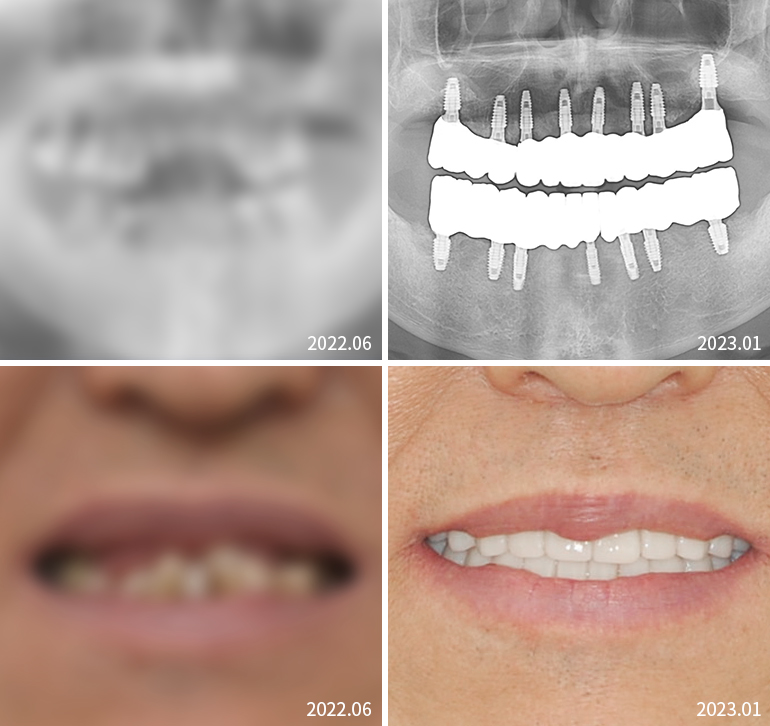

전체임플란트